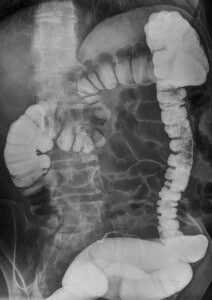

- Рентгенологическое исследование желудка с водорастворимым контрастом позволяет выявить попадание контраста за его пределы. Дополнительным методом исследования при наружных свищах является фистулография - введение контрастного вещества через свищевой ход для оценки его протяженности и локализации. При подозрении на желудочно-ободочный свищ полезной может оказаться проведение ирригографии, рентгенологического исследования толстой кишки с контрастом.

Ирригография для исследования толстой кишки

Желудочно-ободочный свищ в результате прорастания и распада опухоли селезёночного изгиба ободочной кишки. МСКТ